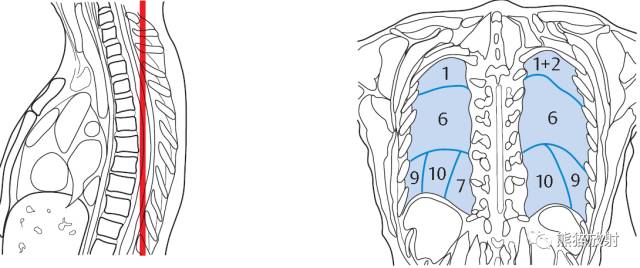

X线平片肺叶/段分布

矢状断层肺段分布

冠状断层肺段分布

下图中:

阿拉伯数字为肺段

绿色结节为淋巴结

蓝色线段为肺段分界

红色线为心包。